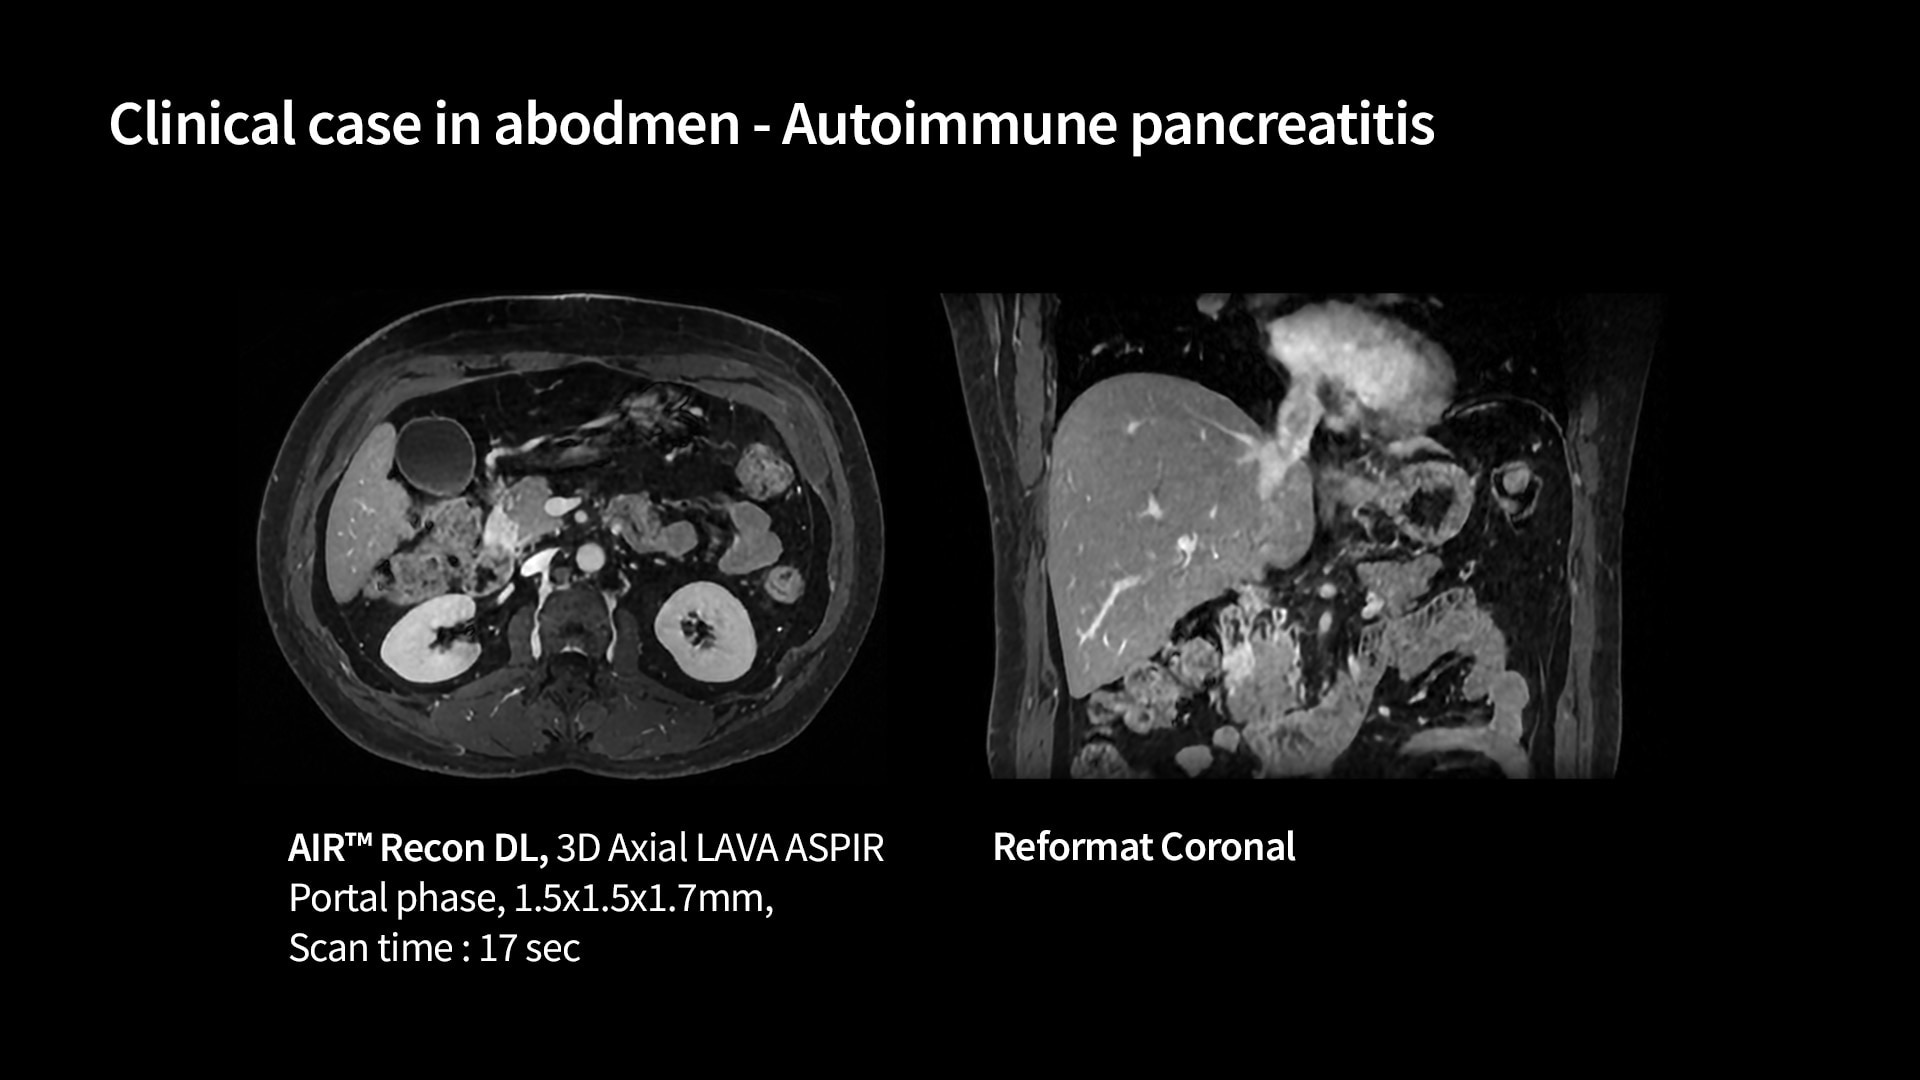

Fast

Advanced acceleration techniques for fast and reliable exams